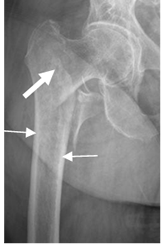

Fig 42. Fractura en osteoporosis.

Rx AP. Postquirúrgico de fractura del fémur. Disminución en la densidad

de la metáfisis distal (Flecha delgada). Cortical normal en el tercio proximal (Flecha gruesa) y engrosamiento de la cortical en la zona de consolidación de la fractura (Punta de flecha).